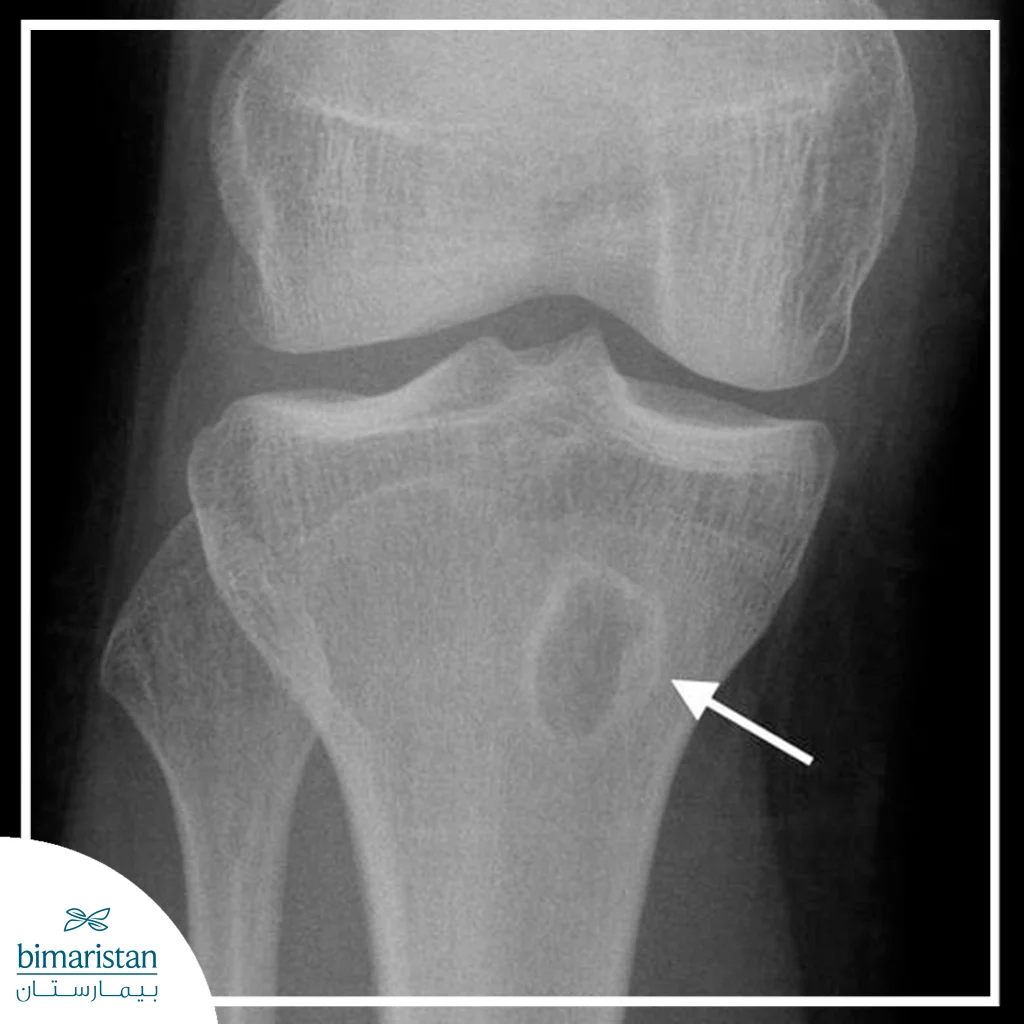

X-ray imaging

An X-ray is a preliminary image that shows bone erosions, bone voids, or dead bone fragments in the late stages, but may be normal in the early stages because visible bone changes take weeks to appear, so it is used as a baseline and then supplemented with more sensitive images or methods if the suspicion is early.